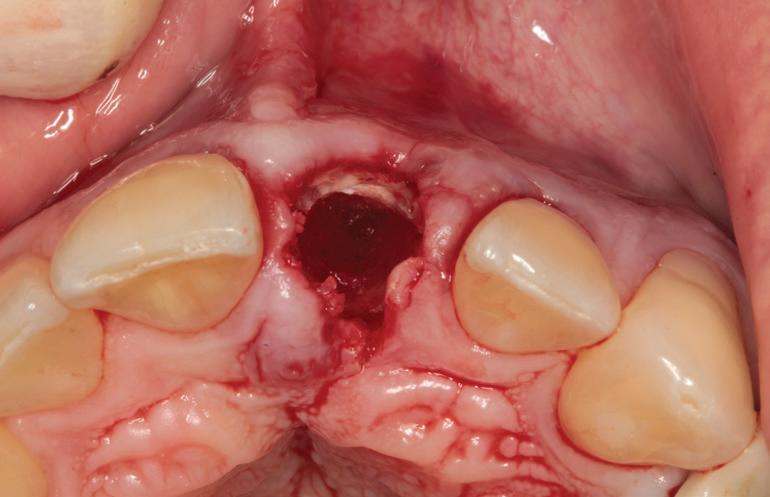

RECUPERAREA planului implantar original. Dacă unul sau mai multe implanturi planificate eșuează, perspectiva reimplantării în locația compromisă poate fi simplificată prin transformarea ghidului chirurgical la nivel osos într-un ghid chirurgical suportat de implanturi în momentul intervenției chirurgicale primare.